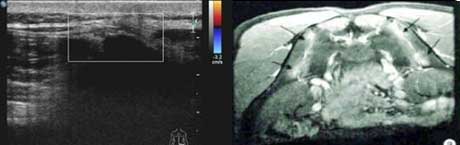

二、清晰显示滑膜炎性病变,提供早期骶髂关节病变线索

骶髂关节炎是强直性脊柱炎的显著特征,早期以滑膜炎性病变为主。肌骨超声对炎症血流十分敏感,可提示活动期强直性脊柱炎患者骶髂关节的异常血流增多变化,反映滑膜炎(滑膜增厚状况、滑膜形态表现、关节腔积液回声形态)表现,为活动性强直性脊柱炎早期骶髂关节病变提供重要线索。

骶髂关节表面不同程度滑膜增厚、回声降低、关节间隙有明显强化灶。

血流信号

骶髂关节内部增厚的关节表面呈点状血流信号,可见多个小动脉点状血流信号。